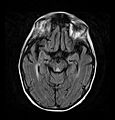

Brain atrophy associated with WKS occurs in the following regions of the brain: the mammillary bodies, the thalamus, the periaqueductal grey, the walls of the 3rd ventricle, the floor of the 4th ventricle, the cerebellum, and the frontal lobe. In addition to the damage seen in these areas there have been reports of damage to cortex, although it was noted that this may be due to the direct toxic effects of alcohol as opposed to thiamine deficiency that has been attributed as the underlying cause of Wernicke-Korsakoff Syndrome.[25]

The amnesia that is associated with this syndrome is a result of the atrophy in the structures of the diencephalon (the thalamus, hypothalamus and mammillary bodies), and is similar to amnesia that is presented as a result of other cases of damage to the medial temporal lobe.[26] It has been argued that the memory impairments can occur as a result of damage along any part of the mammillo-thalamic tract, which explains how WKS can develop in patients with damage exclusively to either the thalamus or the mammillary bodies.[25]

Frequently, secondary to thiamine deficiency and subsequent cytotoxic edema in Wernicke encephalopathy, patients will have marked degeneration of the mammillary bodies. Thiamine (vitamin B1) is an essential coenzyme in carbohydrate metabolism and is also a regulator of osmotic gradient. Its deficiency may cause swelling of the intracellular space and local disruption of the blood-brain barrier. Brain tissue is very sensitive to changes in electrolytes and pressure and edema can be cytotoxic. In Wernicke this occurs specifically in the mammillary bodies, medial thalami, tectal plate, and periaqueductal areas. Sufferers may also exhibit a dislike for sunlight and so may wish to stay indoors with the lights off. The mechanism of this degeneration is unknown, but it supports the current neurological theory that the mammillary bodies play a role in various "memory circuits" within the brain. An example of a memory circuit is the Papez circuit.